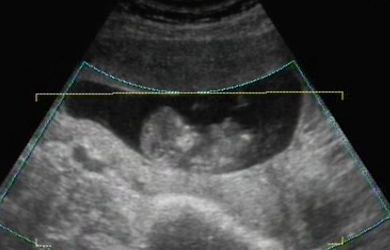

...Szerettem volna veletek megosztani, hogy hogy ficánkolt a drágám, de ilyen rossz hir után most képtelen vagyok!

A lényeg, hogy minden rendben van, és hogy uh szerint még nagyobb is egy héttel! Hallottam kalapálni a kis szivét, láttam a kezecskéit és a lábait...

A nyaki redőnk 0.7 vagyis tökéletes.

Január 23-án megyek a következő vérvételre az integrált teszt miatt!

Van dvd a kicsimről, csináltam nektek belőle képeket:

Kép Kép Kép Kép

Amugy a Bolgárkerék utcában voltam integrált teszten. Ha jól tudom még Juci is ott volt. Isten igazából nem is a 3D-s volt a nagy része a vizsgálatnak, hanem, hogy a Down-kór szűrés. És az egészben az a jó, hogy pont az én dokibácsim van ott az uh-on! :) Mindent megmért, a combcsonttól kezdve a pulzust, az orrcsontot, a fejét... A 3D-sből ennyit csinált amit láttok. Majd késöbb elmegyek mégegyszer, amikor majd a szivét is jól látni, és akkor is csináltatok dvd-t.

És igen, kicsit megnyugodtam. Bár egy mondat megmaradt bennem és tudom, hogy azt fogom várni majd a következő uh-on: "gyomor és hólyag telítődése jelenleg nem ábrázolódik" De szerintem ehhez még kicsik is vagyunk... :(